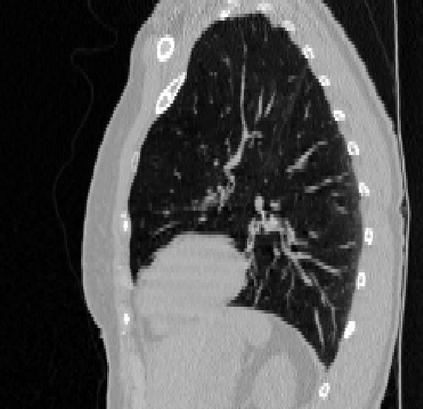

Deformable image registration is a fundamental task in medical image analysis and plays a crucial role in a wide range of clinical applications. Recently, deep learning-based approaches have been widely studied for deformable medical image registration and achieved promising results. However, existing deep learning image registration techniques do not theoretically guarantee topology-preserving transformations. This is a key property to preserve anatomical structures and achieve plausible transformations that can be used in real clinical settings. We propose a novel framework for deformable image registration. Firstly, we introduce a novel regulariser based on conformal-invariant properties in a nonlinear elasticity setting. Our regulariser enforces the deformation field to be smooth, invertible and orientation-preserving. More importantly, we strictly guarantee topology preservation yielding to a clinical meaningful registration. Secondly, we boost the performance of our regulariser through coordinate MLPs, where one can view the to-be-registered images as continuously differentiable entities. We demonstrate, through numerical and visual experiments, that our framework is able to outperform current techniques for image registration.